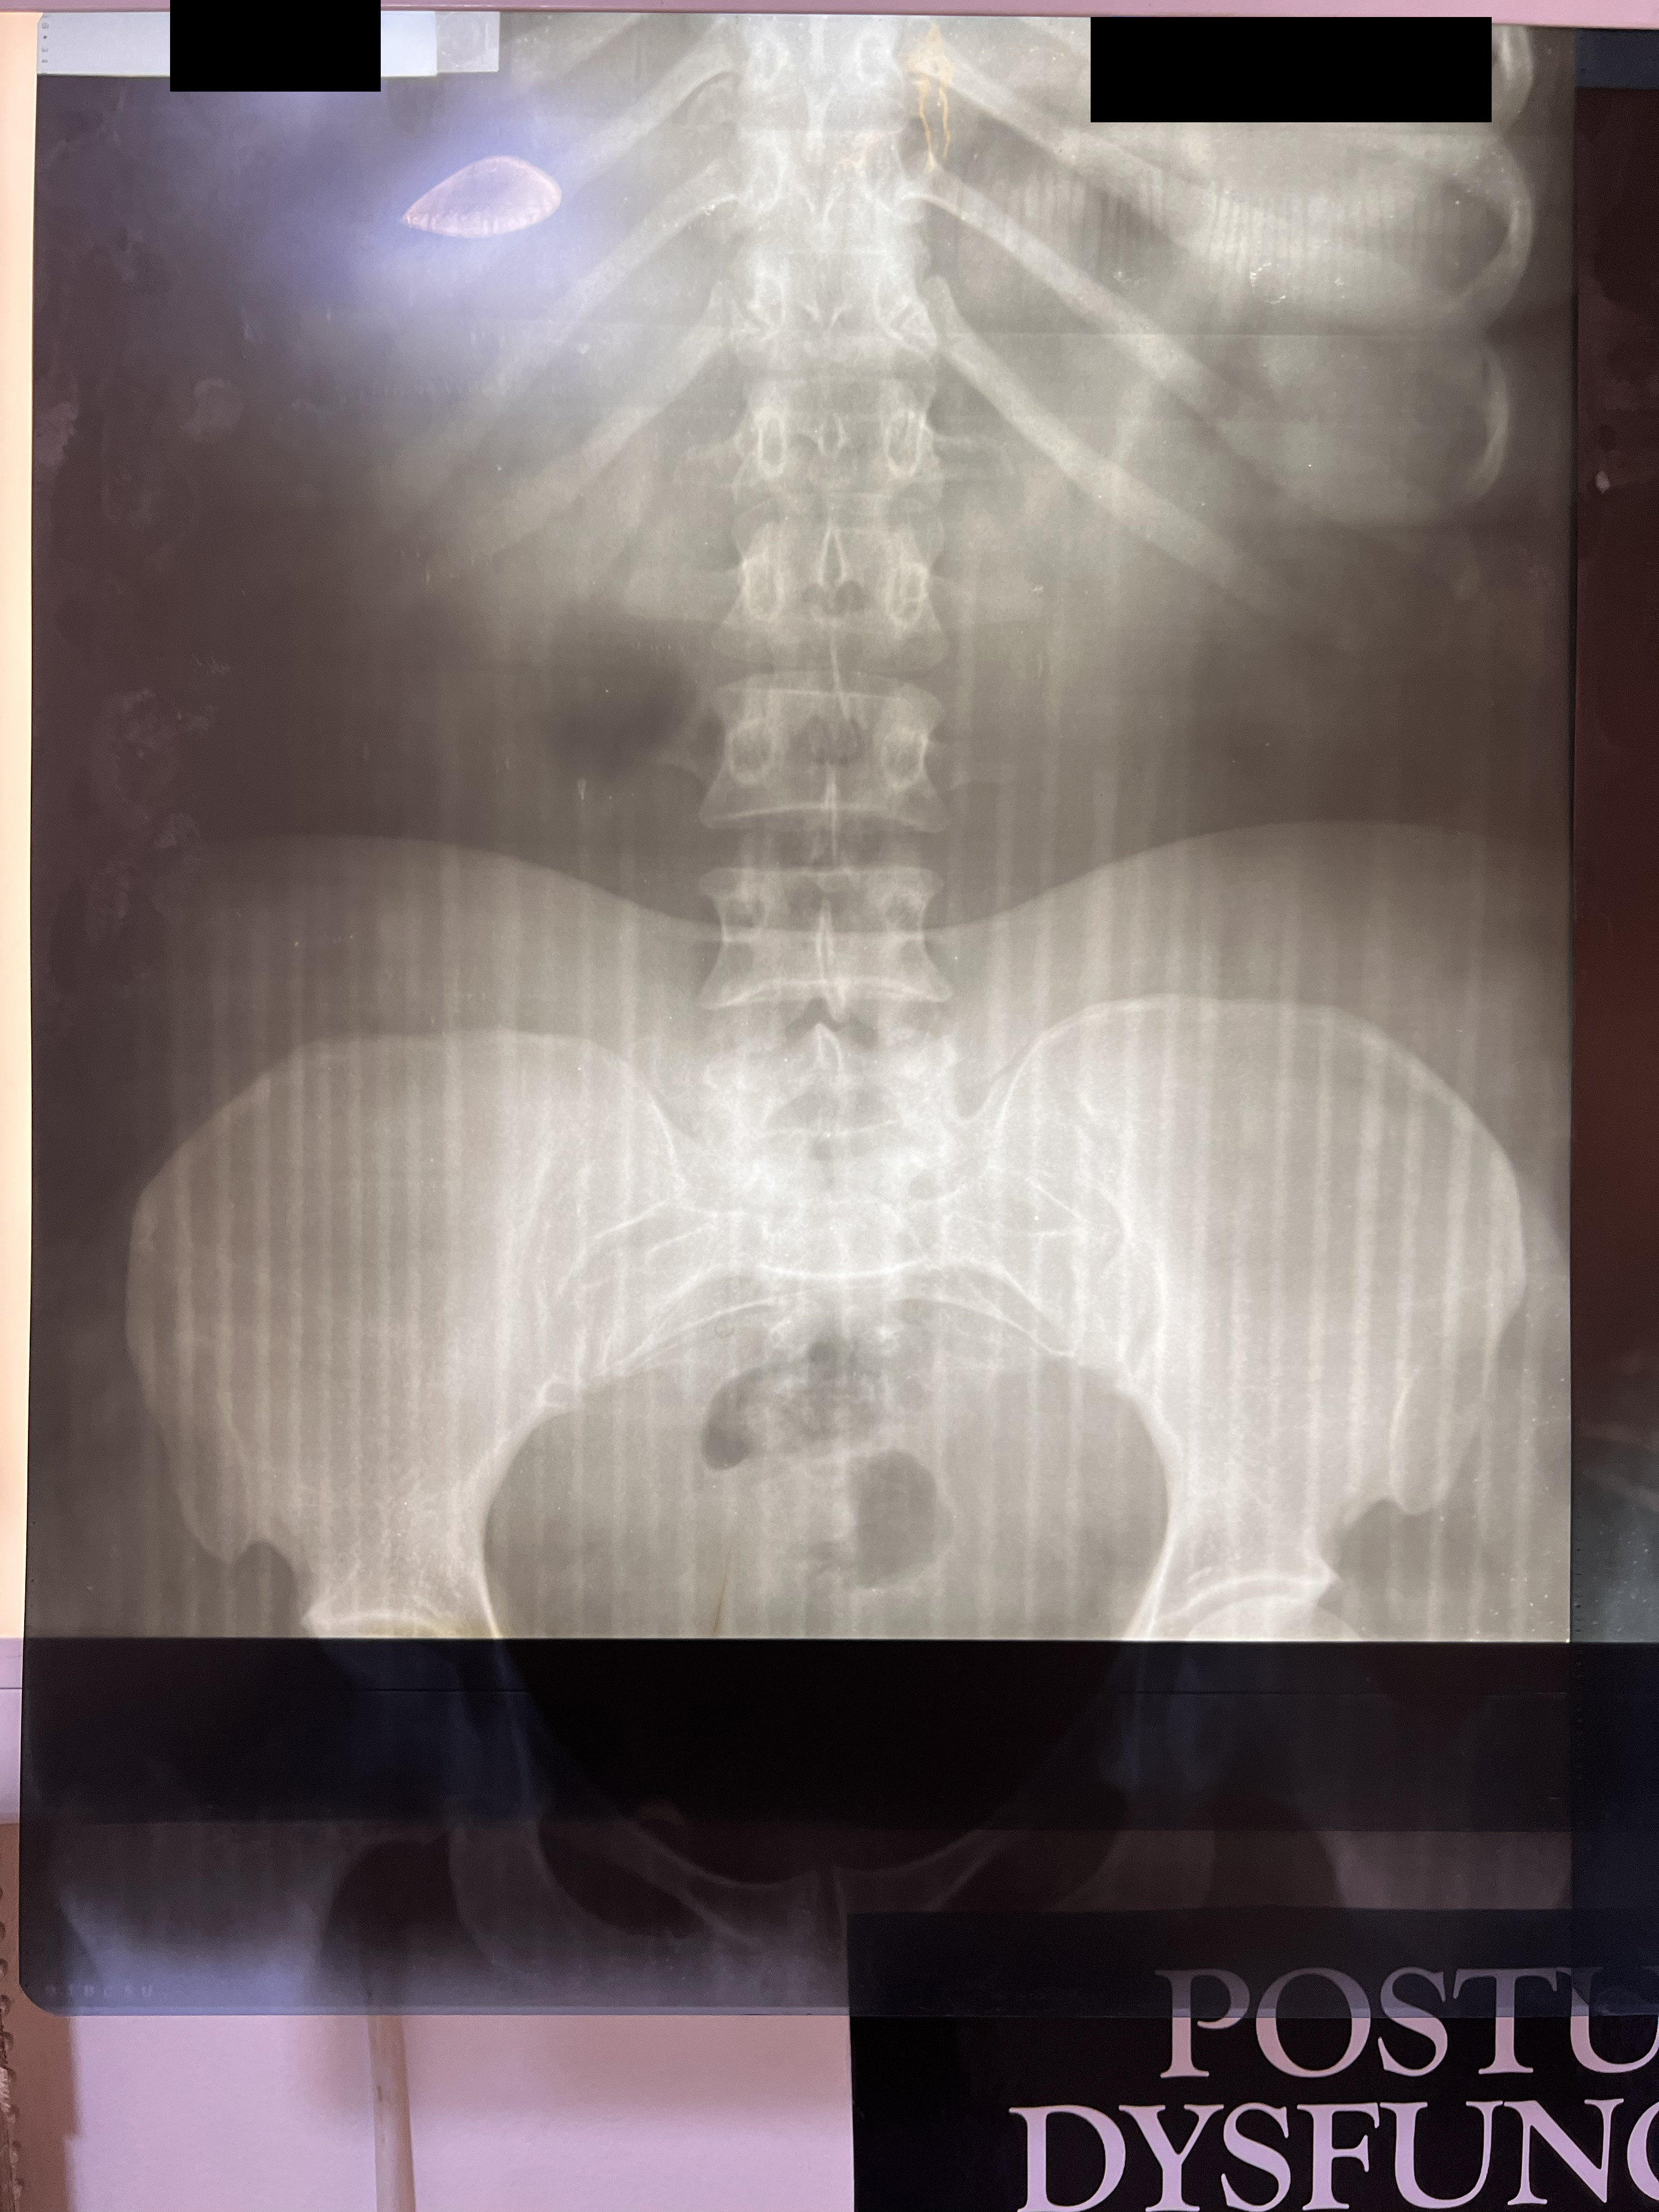

Chiropractic X-Rays

In partnership with Nova Wellness Centre led by Dr Asheley Ashietey in Accra, we conducted chiropractic examinations of 100 women working as kayayei in Kantamanto Market ranging in ages from 15 to 44, with varied experience carrying in the market from those who had been working for a few weeks to some women who had carried bales for 20 years. Nearly every study participant reported significant pain as a result of headcarrying and x-rays indicated spinal deterioration and deformities beginning within months on the job. Such physiological impacts coupled with severely polluted, cramped and violent living conditions set the stage for catastrophic injury.